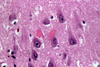

Of the choices offered in the question, only Kearns-Sayre myopathy is a mitochondrial disease. Kearns-Sayre syndrome is caused by large deletions in mitochondrial DNA. Neurologic manifestations include ophthalmoplegia, ptosis, and generalized weakness and often eventually progress to dementia, hearing loss, retinitis pigmentosa, and autonomic neuropathy. Systemic manifestations include heart block, cardiomyopathy, and diabetes. Mitochondrial DNA deletions (as opposed to mutations) are almost always sporadic. Part (a) shows hematoxylin and eosin stain (arrows indicate fibers with an increase in basophilic staining indicative of mitochondrial hyperplasia), part (b) shows modified trichrome stain (arrows indicate ragged red fibers), and part (c) shows cytochrome c oxidase (COX) stain (asterisks mark COX-negative fibers). Electron microscopy (d-f) shows mitochondrial hyperplasia, variation in the mitochondrial shape and size, and mitochondria with crystalline arrays (arrowheads).